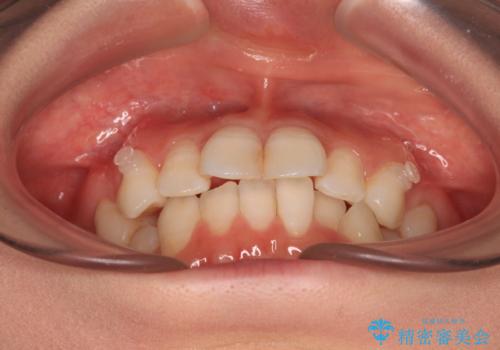

- 上下前歯のデコボコを改善したいとのことで来院された患者様です。

初めの1年くらいは何とか頑張って装着してくださいましたが、途中から変化をあまり感じられなくなり、日々の装着時間は徐々に短くなってしまいました。

前歯のデコボコはもっと改善できましたが、3年半が経過し、初診時と比べたら大幅に良くなったとのことで終了することとなりました。